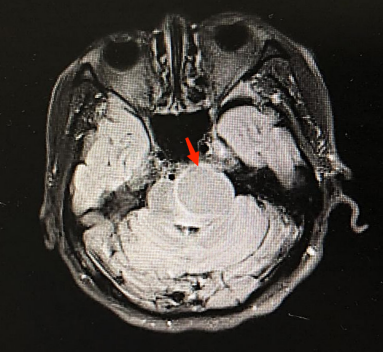

患者,男性,53岁,因“多发性骨髓瘤4月余,欲行第4次化学治疗(化疗)”收入我院血液内科。患者4个月前因“头痛伴左侧听力下降”就诊于我院神经外科,经影像学检查诊断为“左侧三叉神经鞘瘤”(图1),患者的术前实验室检查结果示贫血,经血液科会诊并完善各项检查后诊断为多发性骨髓瘤IgDλ型(DS分期Ⅲ期A组 ISS分期Ⅲ期),化疗方案为硼替佐米+来那度胺+地塞米松,治理期间患者自觉偶有指尖麻木感及眼睛发红,间歇性左眼视物模糊等不适,未予重视。本次住院期间患者诉左眼视物模糊较前加重,遂请眼科会诊。

图1 左侧三叉神经鞘瘤(图中红色箭头所指)

Figure 1 Trigeminal schwannoma on the left (red arrow)